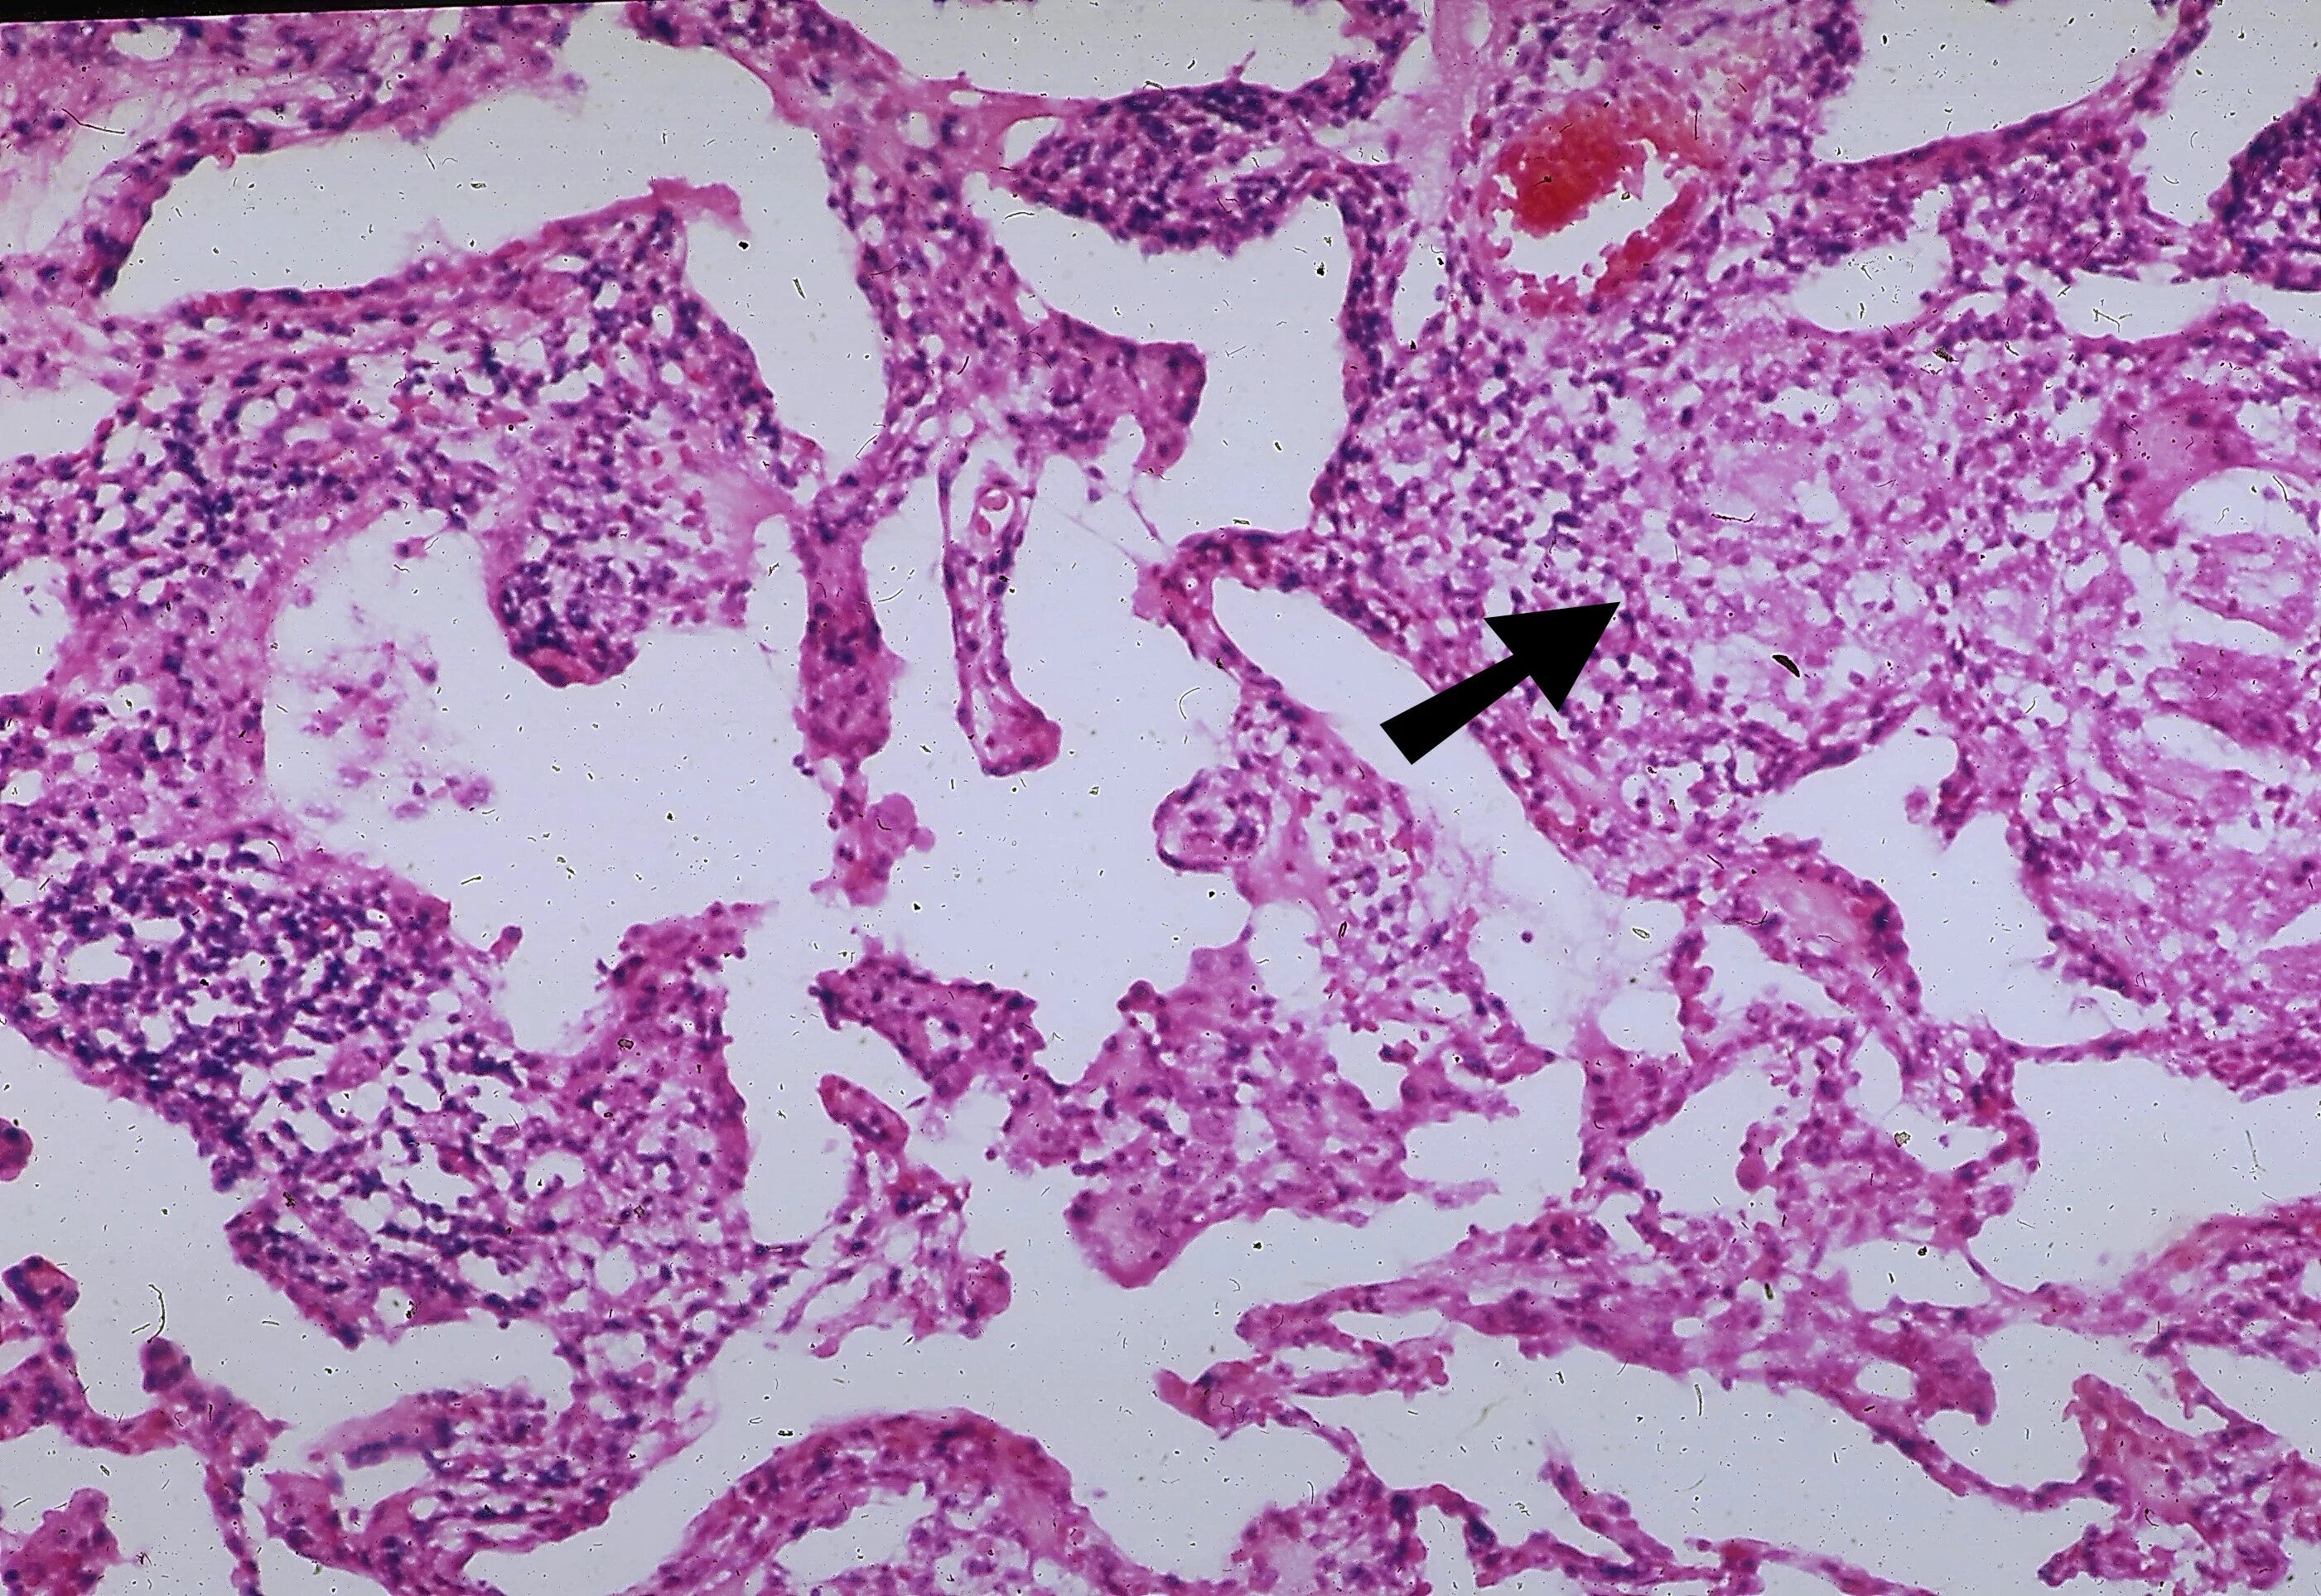

Смешанный периваскулярный инфильтрат при крапивнице